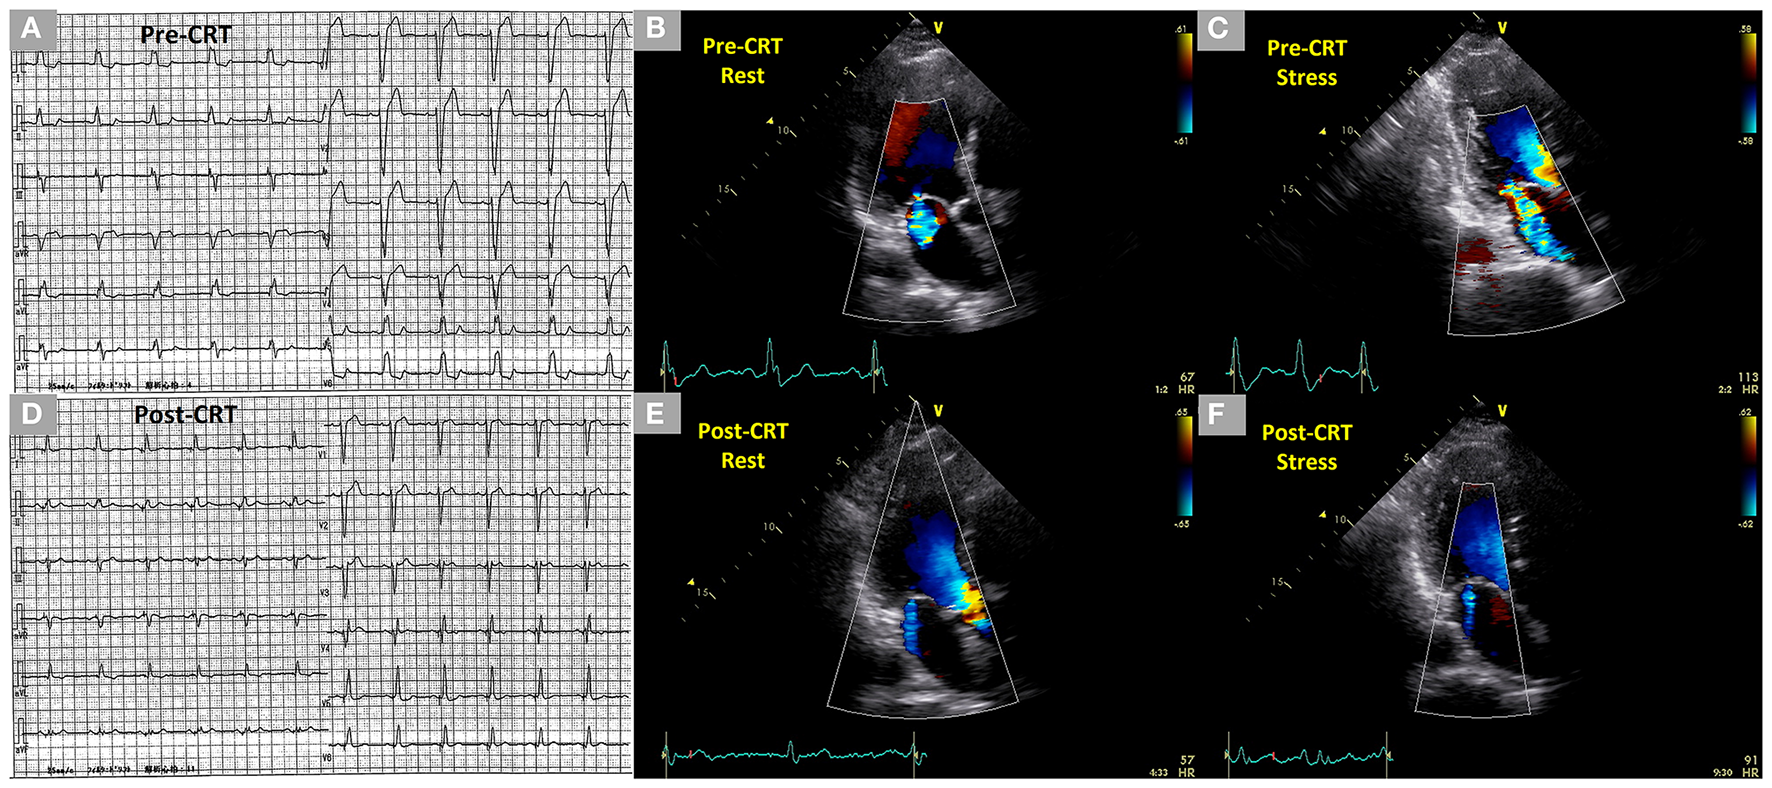

Figure 3

Dynamic changes of SMR during exercise stress echocardiography before CRT and controlled SMR following CRT during exercise stress echocardiography in a 71-year-old male patient who had an anterior old myocardial infarction and heart failure with reduced ejection fraction. (A) Complete left bundle branch block with a QRS duration of 154 ms in the electrocardiogram before CRT. (B,C) Mild SMR (EROA 0.14 cm2) at rest and dynamic moderate-to-severe SMR (EROA 0.32 cm2) under stress in two-dimensional color Doppler images from the three-chamber view before CRT. (D) Non-left bundle branch block with a QRS duration of 128 ms in the electrocardiogram after CRT. (E,F) Trivial SMR at rest and under stress 1 year after the CRT in two-dimensional color Doppler images from the three-chamber view after CRT. SMR, secondary mitral regurgitation; CRT, cardiac resynchronization therapy, EROA, effective regurgitant orifice area.